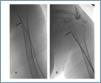

Manual catheter-directed aspiration

First, using ultrasound monitorisation, the access is threaded in the opposite direction from the arterial anastomosis. A guide wire and catheter is used to clear the obstructed segment to connect with the venous area free from thrombus. For PTFE grafts, this area is generally distal to the venous anastomosis. A safety wire is placed and we begin to aspirate thrombi with a large 7 to 9 French catheter (figures 1 and 2). Once the segment is free from thrombi, the catheter is threaded toward the arterial anastomosis and the same operation is repeated. When the access is free from thrombi, we inflate the underlying stenotic areas responsible for the thrombosis with an angioplasty balloon (figures 3 and 4). Medication during the procedure consists of midazolam as a sedative, an antibiotic (third-generation cephalosporin) and a heparin bolus with 3000-5000 IU of sodium heparin. If the patient needs dialysis immediately, the catheter introducers are left in and dialysis is performed using them. LMWH is recommended on non-dialysis days.

Figure 2.